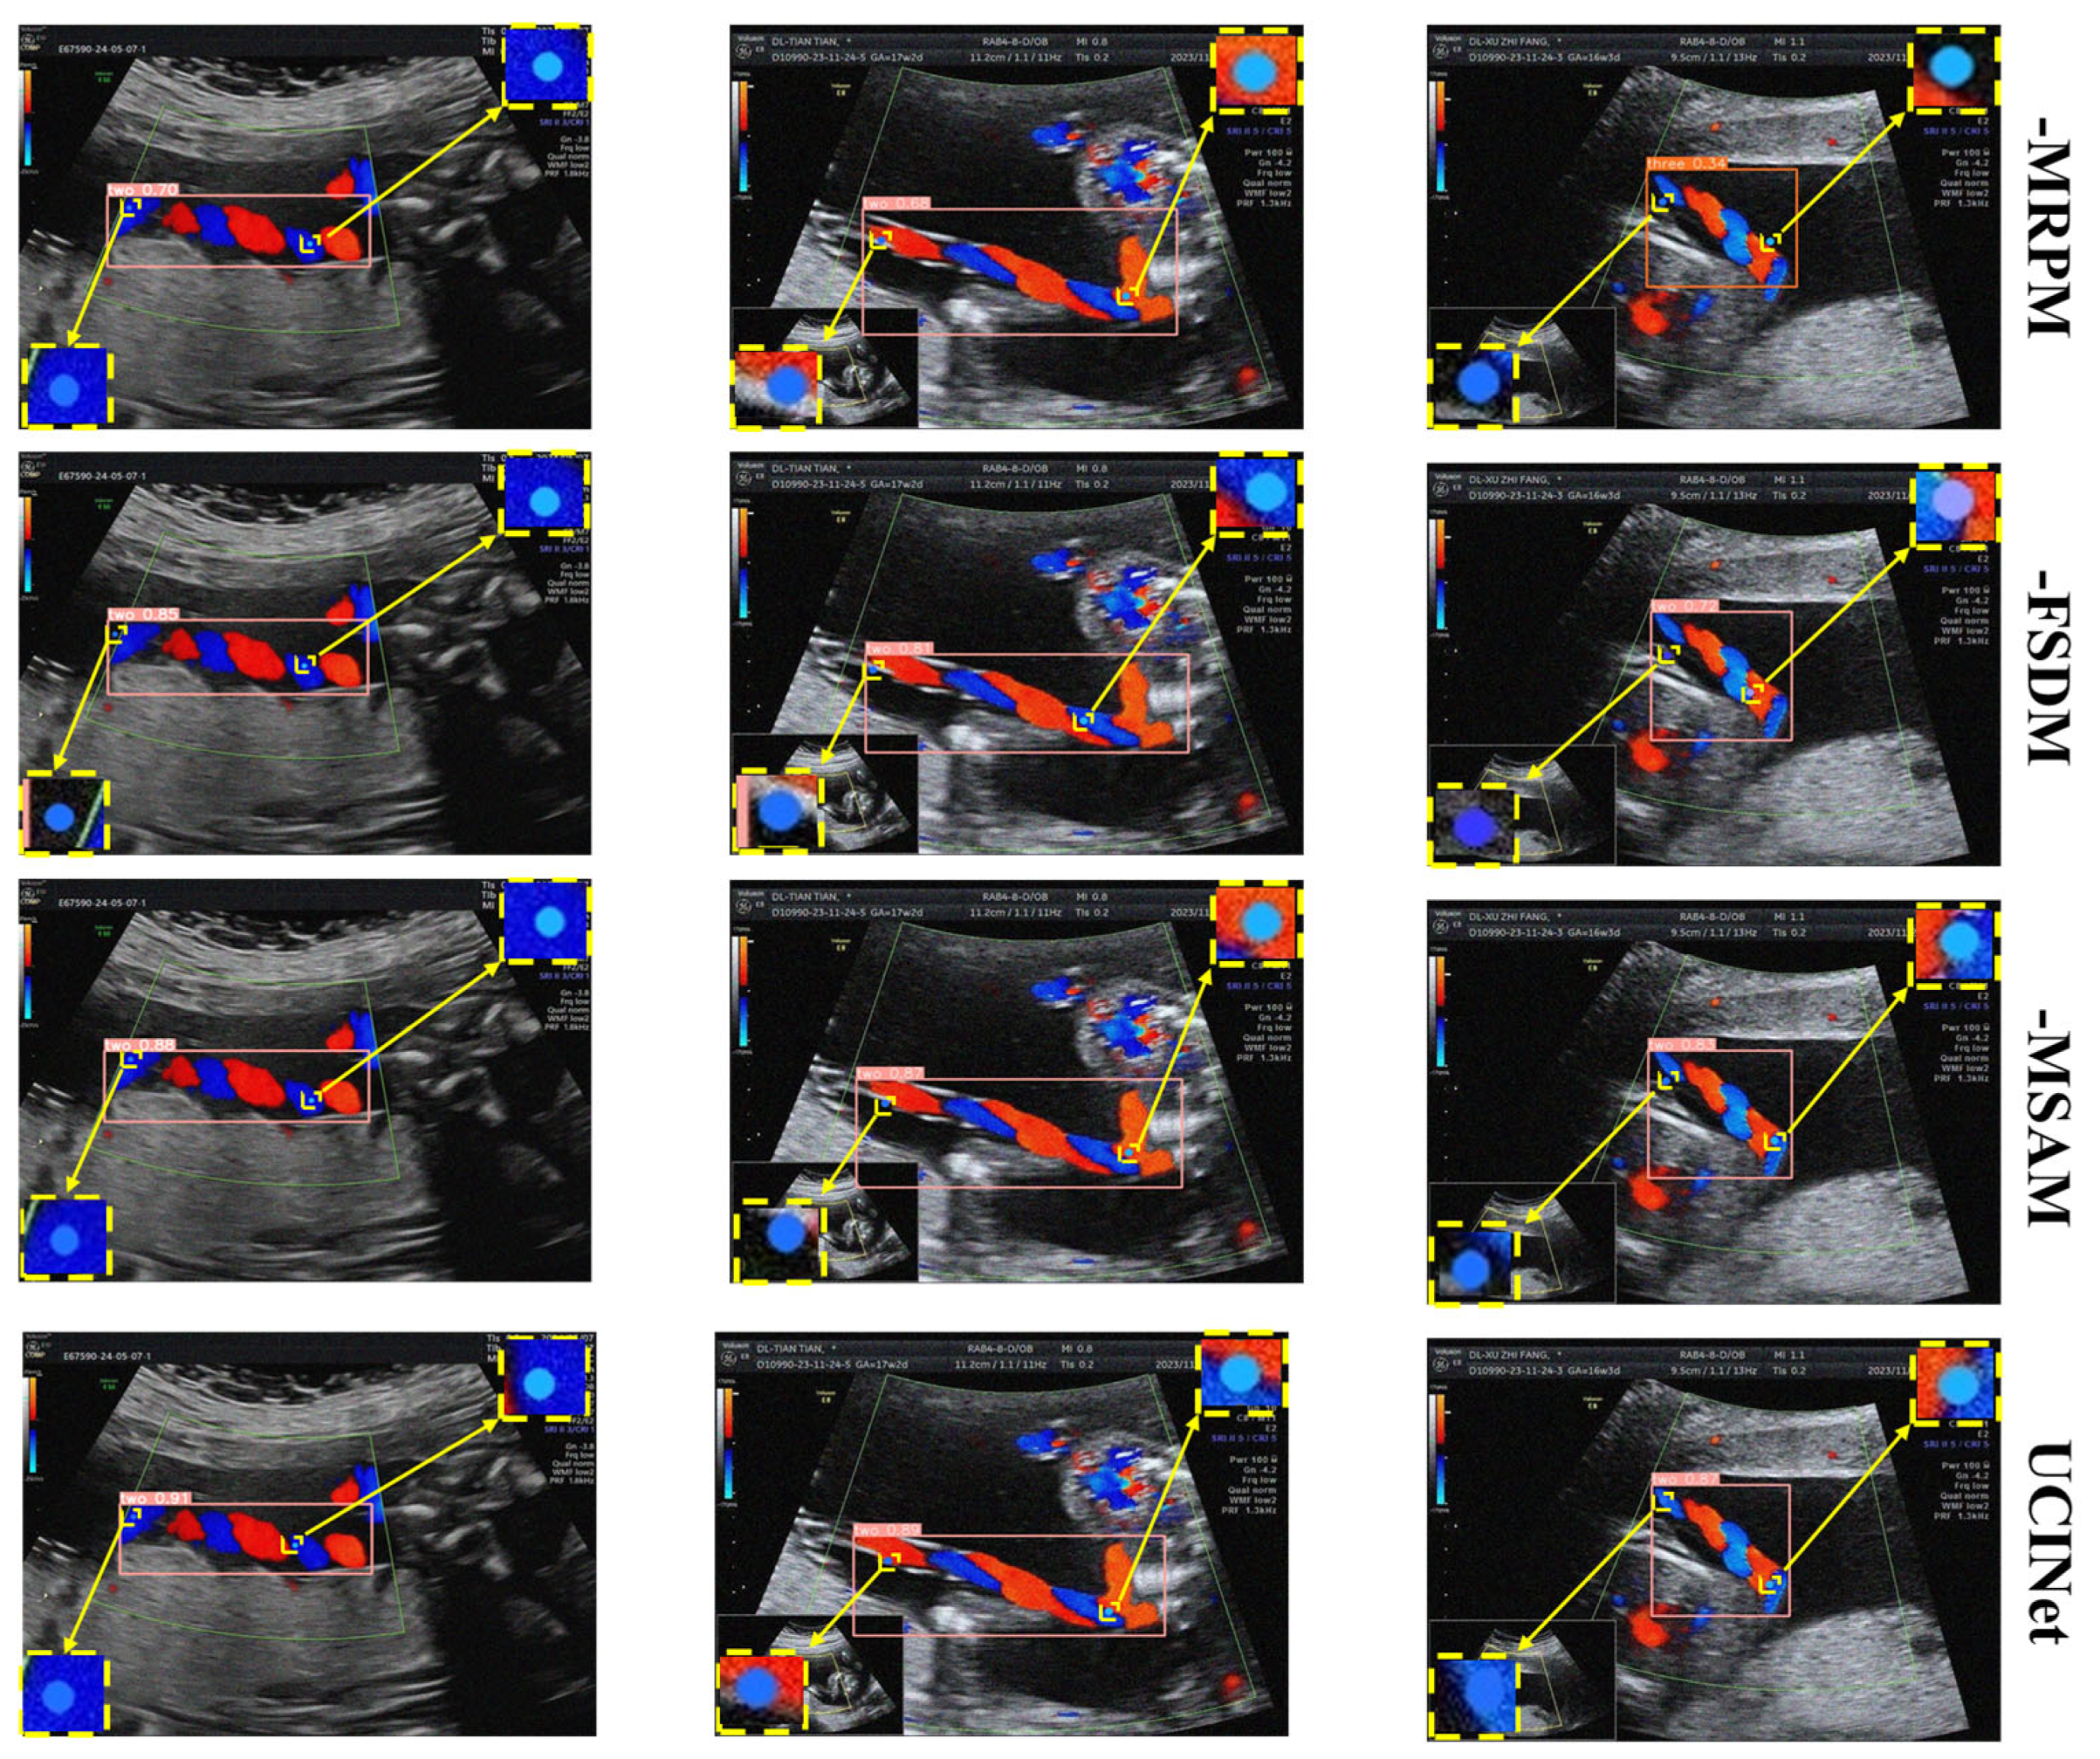

Visual comparisons in Figure 14 further corroborate these findings: without FSDM, the model blurred vessel edges; without MRPM, it incompletely captured coiling structures; without MSAM, it produced inconsistent cross-scale feature fusion. These results demonstrate that all three modules are indispensable and mutually complementary, and their joint inclusion delivers statistically robust and clinically meaningful improvements in detection and keypoint localization.

Figure 14. Visualization of the effects after removing each module.